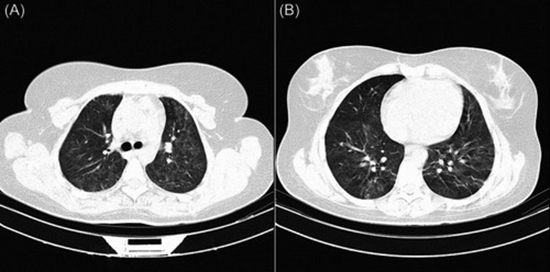

Methods: A case-control of 107 immunocompromised and 107 immunocompetent COVID-19 patients matched for age and sex with either positive RT-PCR or clinical-radiological findings suggestive of COVID-19 enrolled in the study. Their initial clinical features, laboratory findings, chest CT scans, and short-term outcomes (hospitalization time and intensive care unit [ICU] admission) were recorded. In addition, pulmonary involvement was assessed with the semi-quantitative scoring system (0-25).

Results: Pulmonary involvement was significantly lower in immunocompromised patients in contrast to immunocompetent patients, especially in RLL (p = 0.001), LUL (p = 0.023), and both central and peripheral (p = 0.002), and peribronchovascular (p = 0.004) sites of lungs. Patchy (p < 0.001), wedged (p = 0.002), confluent (p = 0.002) lesions, and ground glass with consolidation pattern (p < 0.001) were significantly higher among immunocompetent patients. Initial signs and symptoms of immunocompromised patients including dyspnea (p = 0.008) and hemoptysis (p = 0.036), respiratory rate of over 25 (p < 0.001), and spo2 of below 93% (p = 0.01) were associated with higher pulmonary involvement. Total chest CT score was also associated with longer hospitalization (p = 0.016) and ICU admission (p = 0.04) among immunocompromised patients.

Conclusions: Pulmonary involvement score was not significantly different among immunocompromised and immunocompetent patients. Initial clinical findings (dyspnea, hemoptysis, higher RR, and lower Spo2) of immunocompromised patients could better predict pulmonary involvement than laboratory findings.